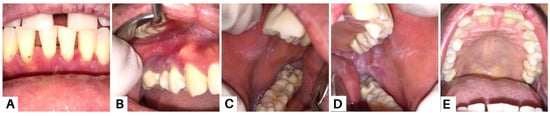

Figure 8.

Clinical presentation of the oral mucosa in the eighth week; all lesions revealed improvements (A–E). Methylprednisolone was given at a daily dose of 16 mg, and was then gradually tapered over four weeks. The patient was also prescribed folic acid 1 mg, omeprazole 50 mg, vitamin D3 400 IU, and AZA 50 mg twice daily for the last two weeks. The patients were also instructed to maintain oral hygiene and use alcohol-free mouthwashes containing chlorhexidine gluconate 0.12%. Supra- and subgingival scaling were also carried out. Strategies for the management of PV aim to achieve and maintain complete remission with minimal side effects [20]. Systemic corticosteroid therapy is the most commonly used and well-established treatment due to its high efficacy and rapid control. We also administered AZA to the patient due to its efficacy as a corticosteroid-sparing agent in autoimmune bullous diseases, particularly in PV [4,15].